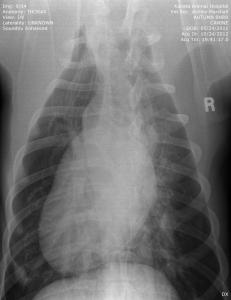

UPDATE: I know I have much to update in BHRR's Autumn's blog and before I go to bed in the wee hours; I shall update her blog plus add photos from her x-rays – taken of both legs, chest, back, legs, heart etc. on October 24th, 2012 and you can find them below! 🙂

YET, today is a very special day for her…..SPAY day! She is still thin, no doubt about that yet, we are in that catch twenty-two….due to the hormones, she continues to lactate and be in a state food going to produce milk instead of putting in weight. YET, being thin, makes it more risky to spay. 🙁 She needs to gain weight yet, cannot really well as she is in this false pregnany hormone out of balance state. So, we are about 10 or so more pounds that we were with her weight and the go ahead has been given to spay.

From there, we are putting our creative hats on as she will need two cruciate surgeries – $6,000-$7,000+ – and the specialist is still looking at those eyes and what is going to be best….